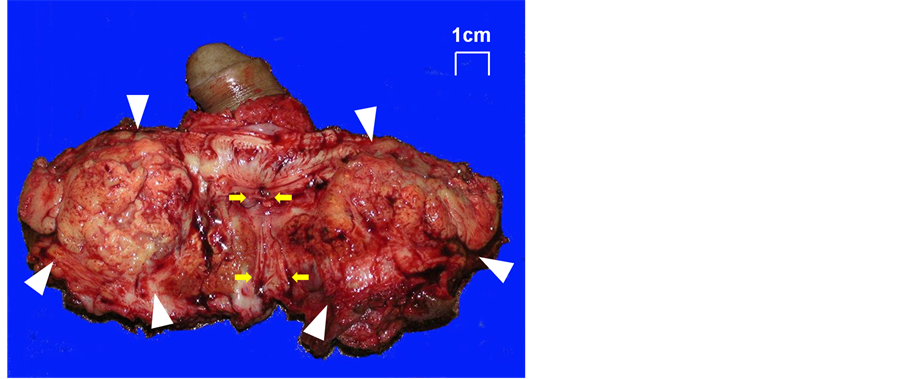

A 69-year-old man with no past medical history was referred to our hospital complaining of dysuria and gross hematuria associated with a rapidly growing perineal mass. Physical examination revealed a stiff mass in the perineum. Digital rectal examination showed no abnormal findings. Serum laboratory data showed inflammatory findings, and among several tumor markers measured, only the SCC antigen level was slightly high at 2.4 ng/mL. Magnetic resonance imaging (MRI) examination revealed a tumor (45 × 52 × 55 mm) posterior and inferior to the pendular urethra with a cystic lesion inside, which was invading the corpusspongiosum (Figure 1). Urine cytology was positive, suggesting SCC. Cystourethroscopy revealed a constriction at the posterior urethra but no clear finding of urethral tumor. The patient then developed urinary retention and for which percutaneous cystostomy was performed. Percutaneous tumor needle biopsy showed SCC. Tumor resection and total penectomy were then performed. The bilateral testes were preserved. The excised tumor appeared as a solid and grayish mass, approximately 5 cm in size, with a yellowish granulomatous lesion next to the urethra (Figure 2). Pathohistological findings revealed well-differentiated SCC arising from the paraurethral region (Figure 3(A)). Neither the scrotal skin nor the urethra was directly infiltrated by the tumor (Figure 3(B), Figure 3(C)), while the urethral constriction was involved with the granulomatous lesion which was determined to be inflammation associated with tumor spillage (Figure 3(D)). The surgical margin was negative. Postoperatively, no additional treatment was administered. As of 70 months after surgery, the SCC antigen level was normal, and the patient remained free of disease.

Figure 2. Macroscopic appearance of the tumor. The tumor is solid and grayish, apart from the urethra. Arrowheads indicate tumor and arrows indicate urethra.